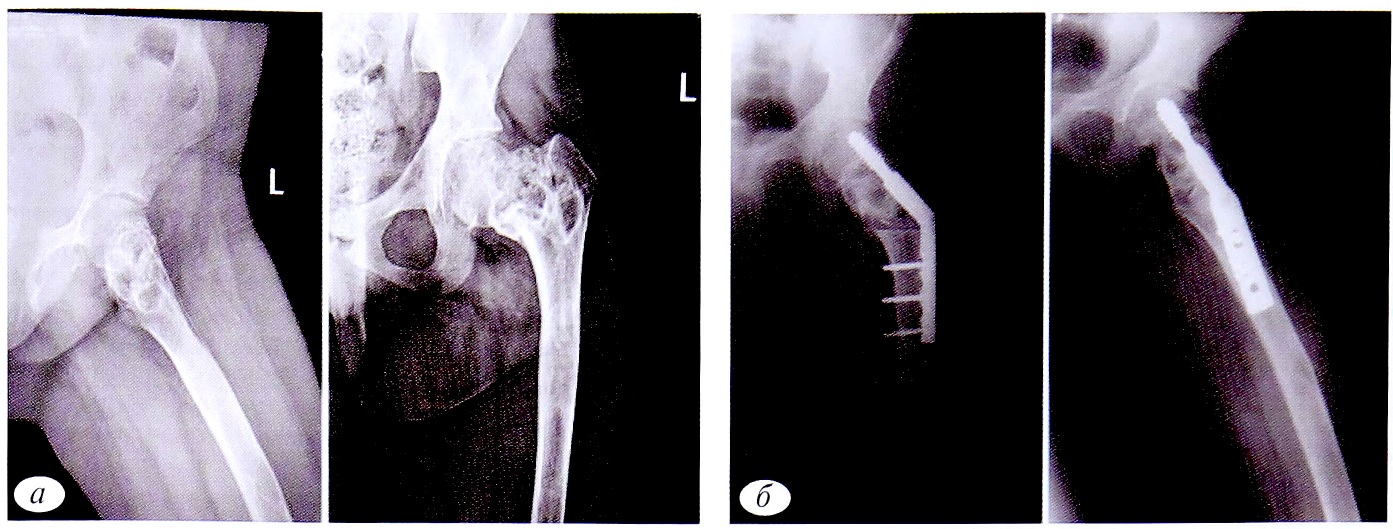

Рис. 5. Пациентка М.,14 лет. Диагноз: патологический перелом шейки левой бедренной кости на фоне фиброзной дисплазии. а — рентгенограммы левого тазобедренного сустава в прямой и аксиальной проекциях до операции; б — в прямой и аксиальной проекциях после операции: краевая резекция проксимального отдела левой бедренной кости, аллопластика, металлоостеосинтез пластиной DHS.

Fig. 5. Patient М.,14 years old. Diagnosis: pathological fracture of the left femur neck due to fibrous dysplasia. a — radiographs of the left hip joint in direct and axial projections before surgery; б — radiographs of the left hip joint in the direct and axial projections after surgery: edge resection of the proximal part of the left femur, alloplasty, metallosteosynthesis with a DHS plate.